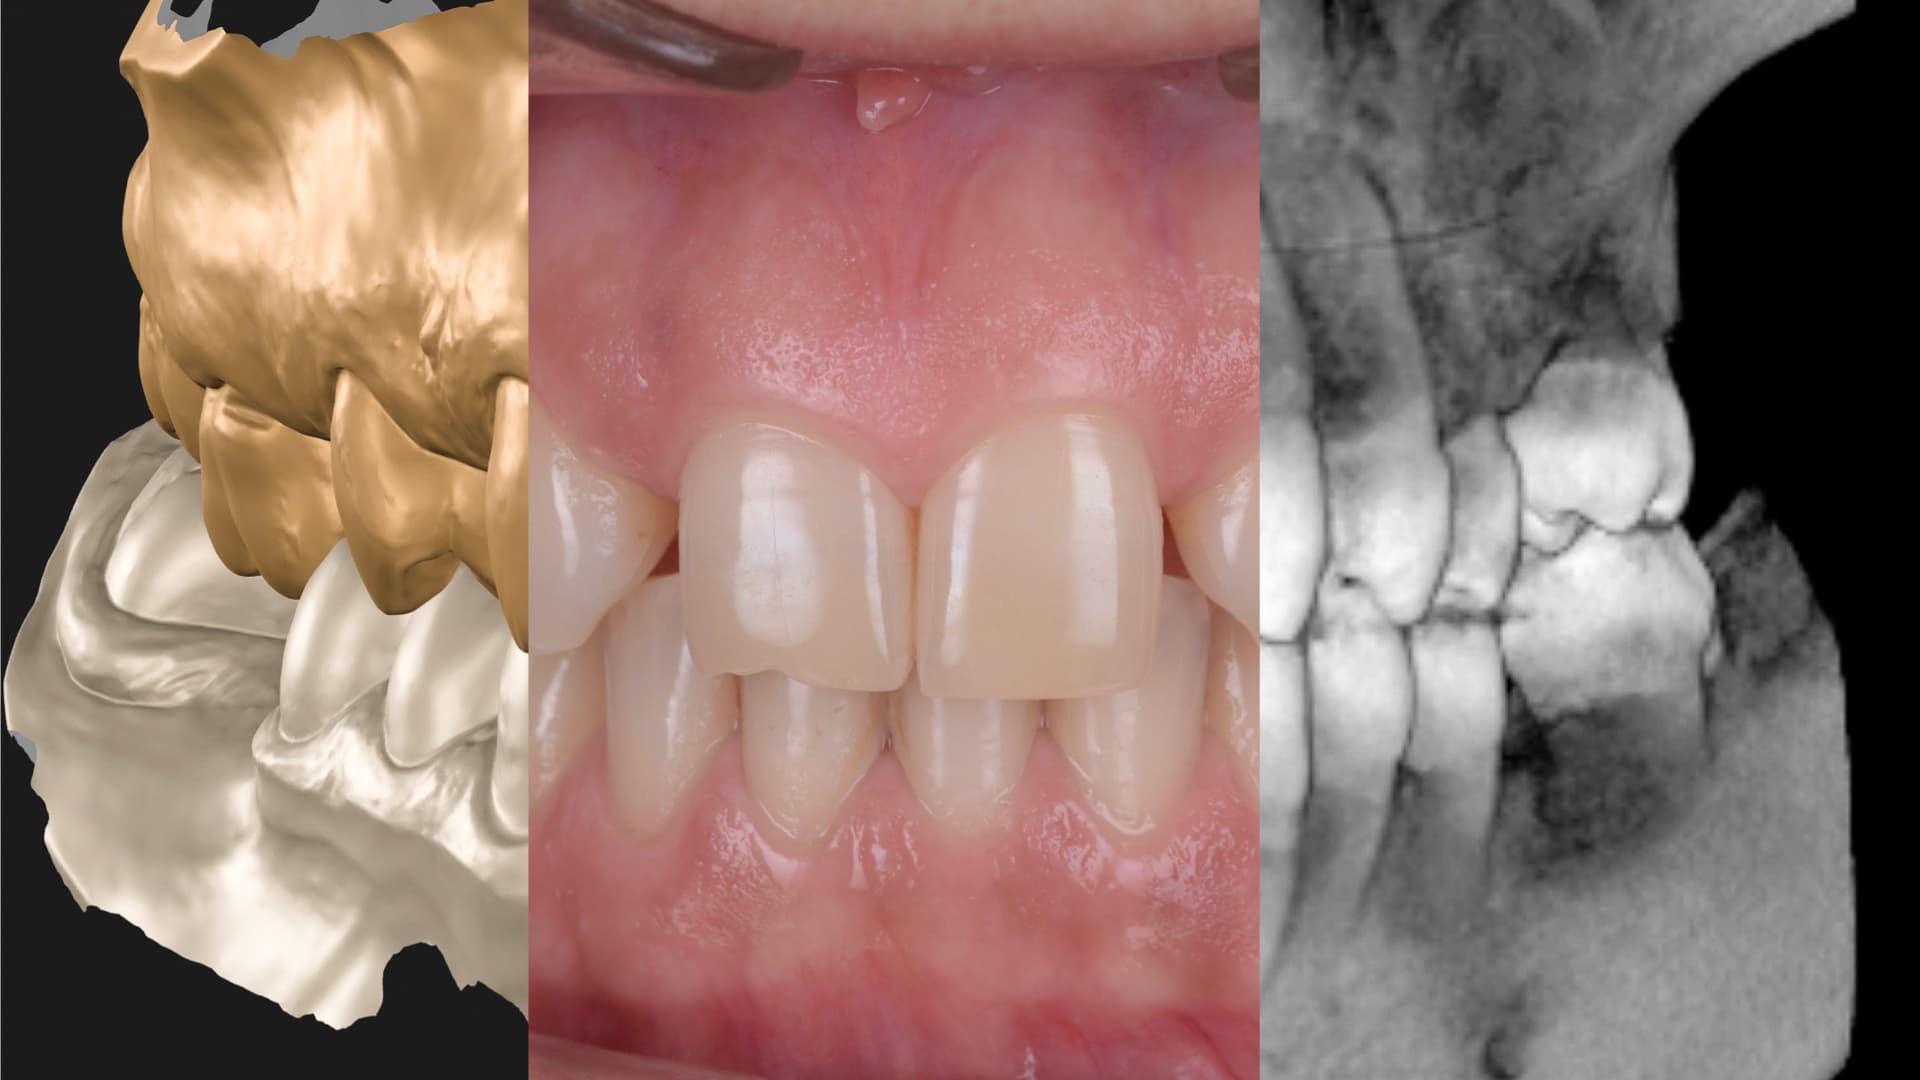

Every aligner case begins with a facially guided digital plan. Using 3D scans, bite analysis, and photos, we simulate the ideal outcome before moving a single tooth. This ensures that every shift supports not only alignment, but also future restorative needs, gum levels, and bite stability.

Fully Digital Workflow

From simulation to retainers, powered by technology.

Our aligner workflows are fully digital, which means greater comfort, accuracy, and efficiency. Everything is stored and reproducible, giving you long-term flexibility.

Before treatment begins, you preview the final result. Our mock-ups and simulations let you understand the full plan—visually and functionally—so you can make an informed decision.